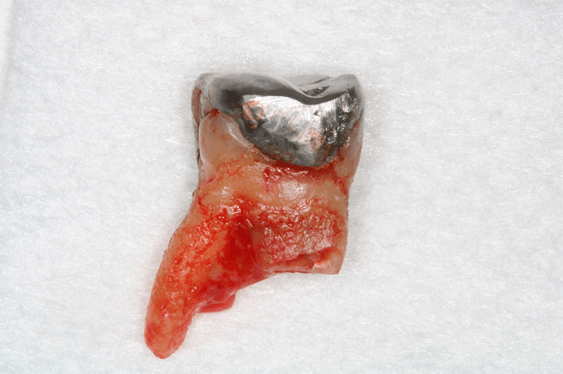

Avaliamos o desempenho do biomaterial de hidroxiapatita com colágeno tipo I (Extra Graft XG-13®) na manutenção do volume alveolar.

A aplicação como o caso clínico abaixo se mostrou uma técnica acessível a todos cirurgiões dentistas, pois se trata de um procedimento de simples execução e acessível. Logo, deveria constar na clínica diária.